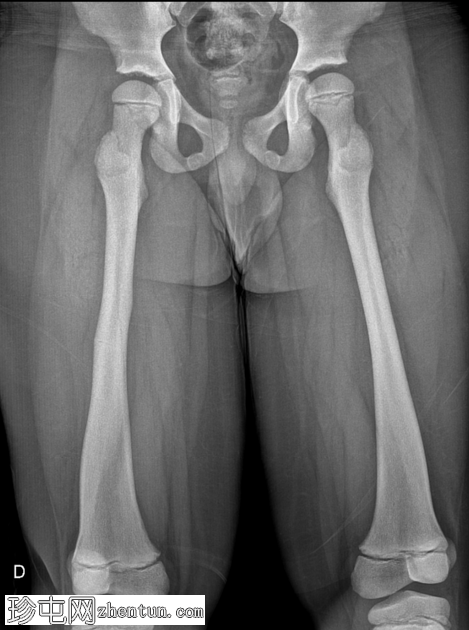

右大腿隐痛持续数日。已知有致密性骨发育不良病史。

年龄:10岁

性别:男

X光片

正面

弥漫性骨密度增高。

长骨髓质变窄。

右股骨不完全性骨折,骨折后功能不全。

双侧胫骨骨干先前骨折后出现骨重塑。